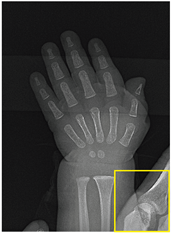

A set of twenty images is selected to assess the effectiveness of the method developed in this work. This set is divided into two groups: the first includes 10 natural scene images extracted from the Kodak dataset [43], specifically from kodim01 to kodim10 (hereinafter referred to as Natural1 to Natural10, respectively). The second group consists of 10 medical images (referred to as Medical1 to Medical10, respectively) selected from various libraries, including brain images [44,45], blood composition images (white blood cells of the basophil and eosinophil types) [46,47], X-rays [48], ocular nodules [49], dental infections [50], microphotographs of pulmonary blood vessels [51], and traumatic forearm positioning [52].

For medical images, there are instances where differences are more perceptible. For example, in the Medical3 image, the maximum contrast solution makes it difficult to visualize the internal details of the basophil (a white blood cell highlighted in the box), which could result in a less accurate interpretation. In contrast, the knee and maximum detail solutions provide a clearer view of the interior of the white blood cell. Similarly, in the Medical5 image, the maximum contrast solution highlights the hand and arm bone structures. However, the maximum detail image offers a more precise view of the internal structures within the bones (see the highlighted region), which is crucial for a more detailed evaluation. Another notable example is the Medical8 image, where the maximum detail solution offers a more detailed view of the internal structure of the eosinophil (another type of white blood cell). However, the maximum contrast image improves the visibility of red blood cells. As shown in the yellow box, this solution reveals a red blood cell that is nearly imperceptible in the other solutions. An interesting case is the Medical6 image, where only a few non-dominated solutions are present on the Pareto front. Despite the similarities among the preferred solutions, the nodules are much more perceptible in the enhanced images than in the original image, as observed in the highlighted region.